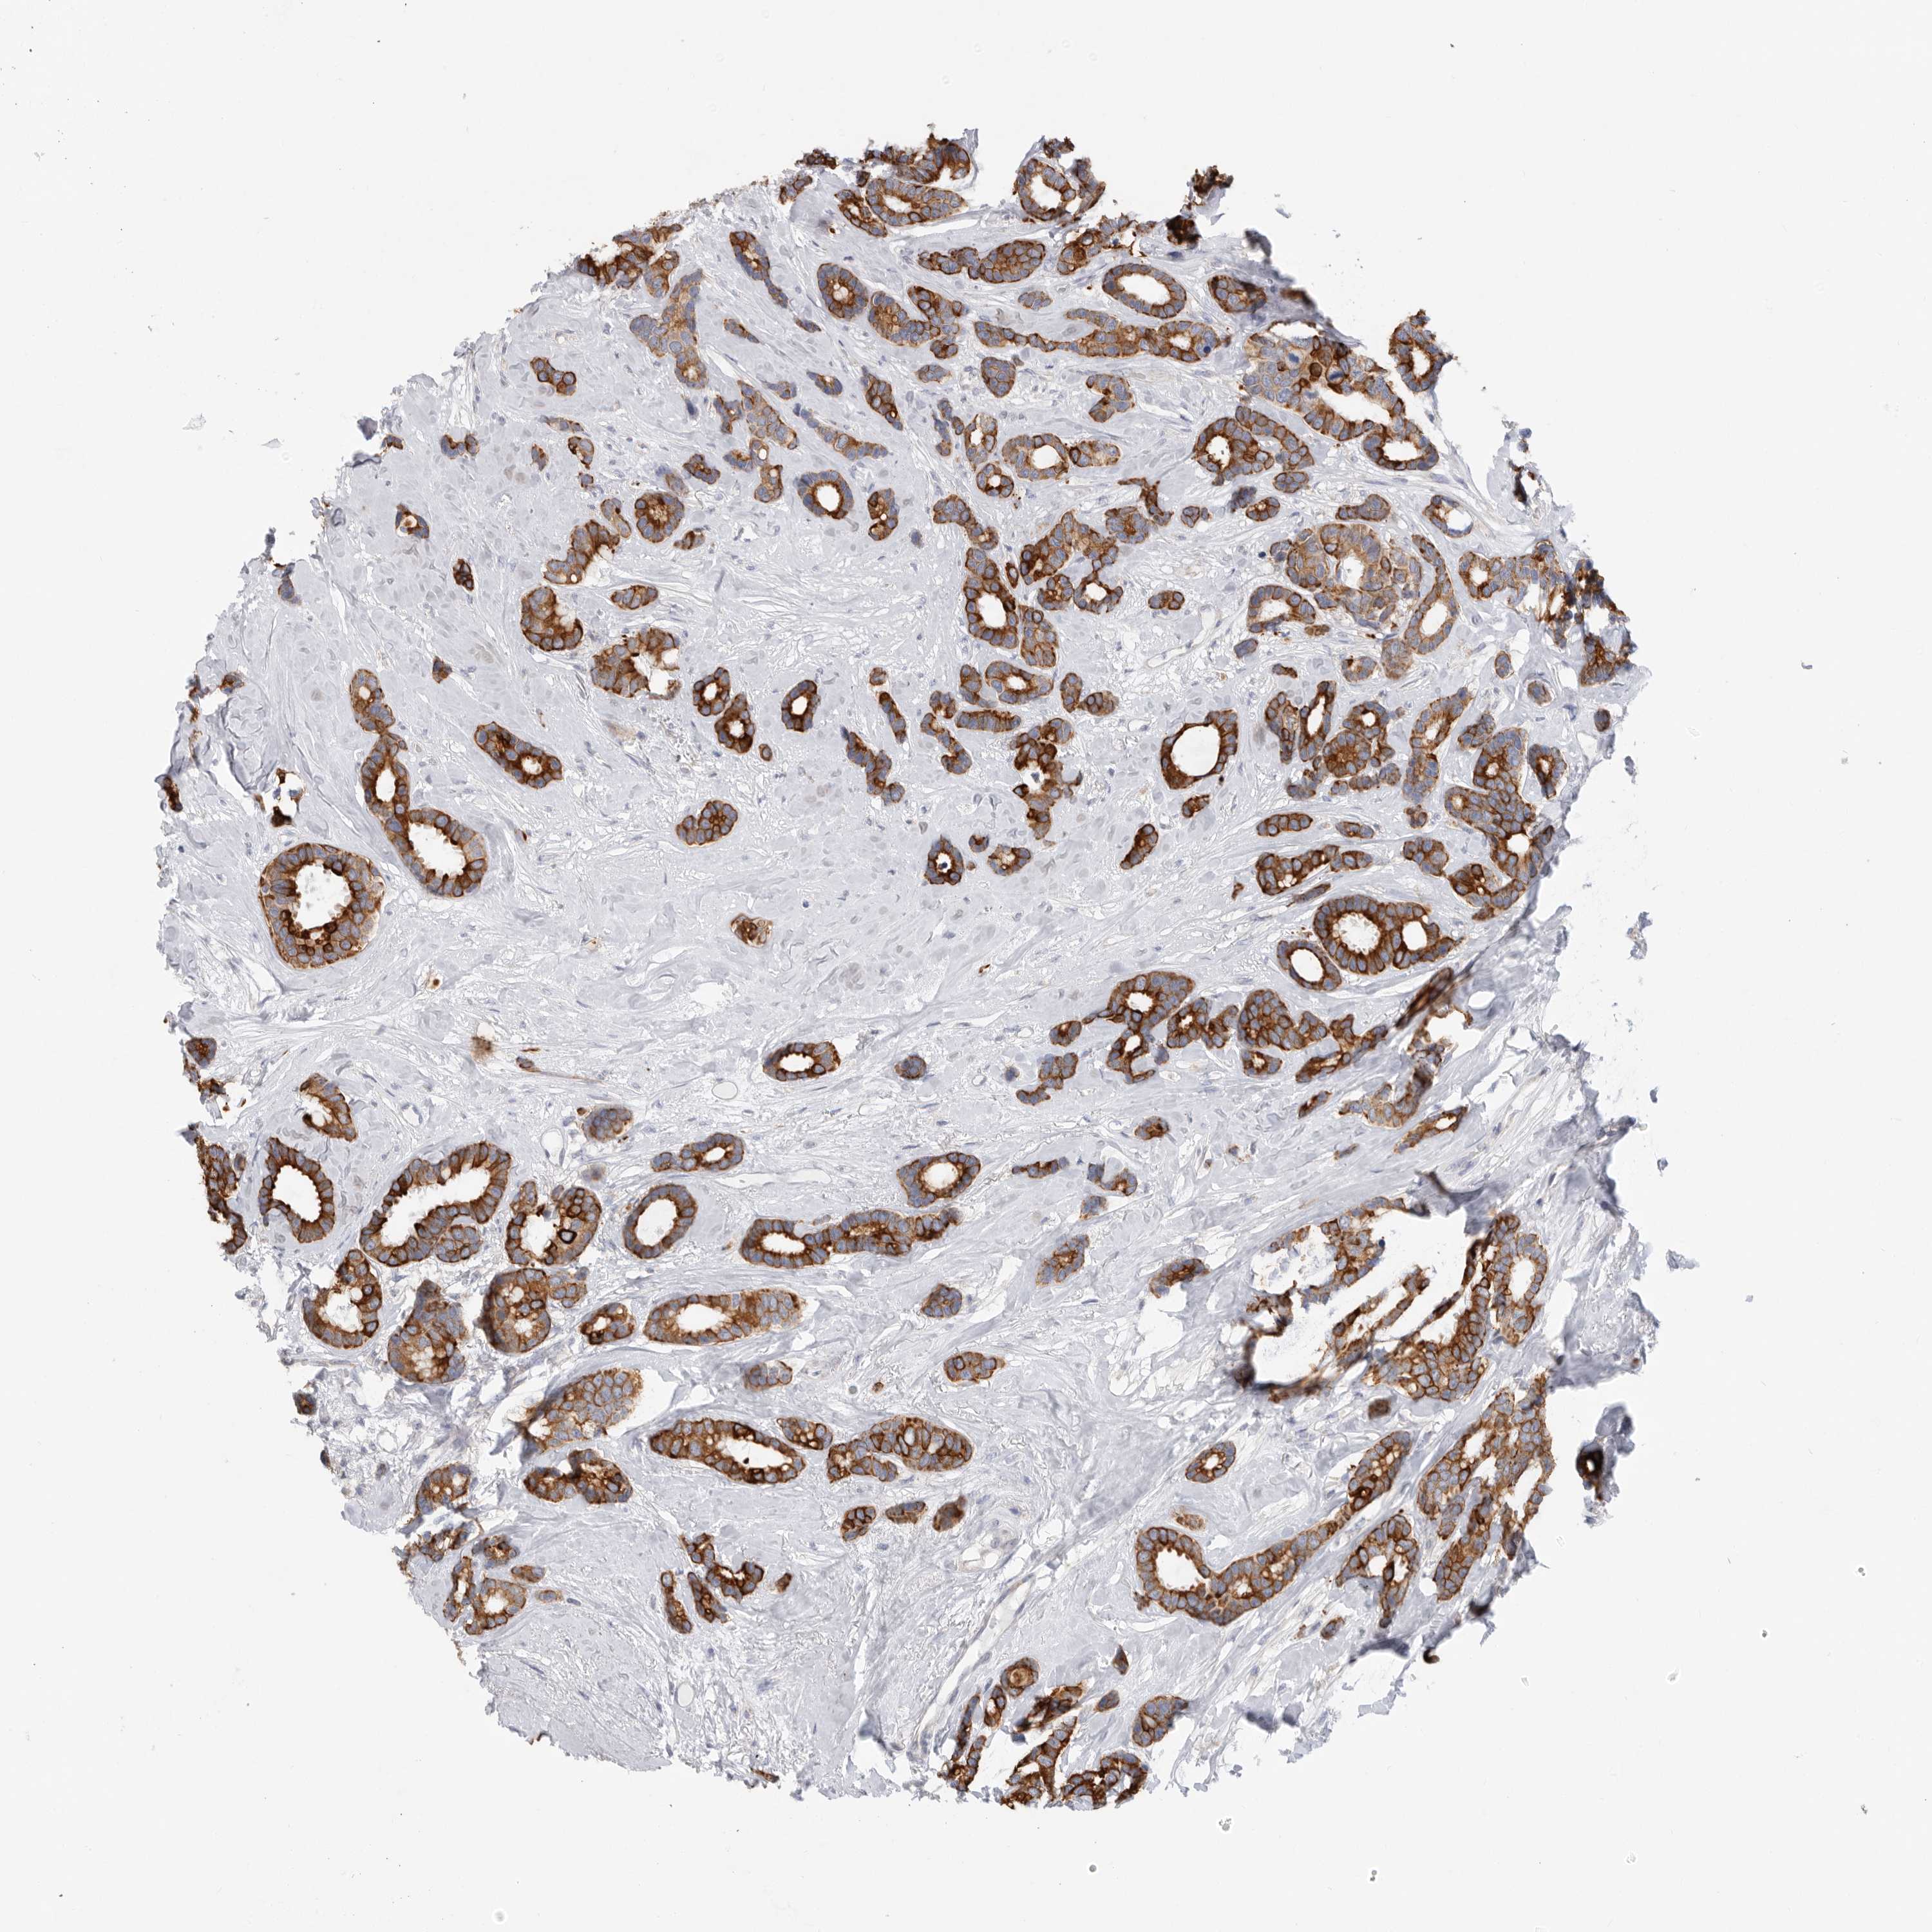

CANCER BREAST CANCER Show tissue menu

BRCA TCGA BRCA VALIDATION PROTEIN EXPRESSION